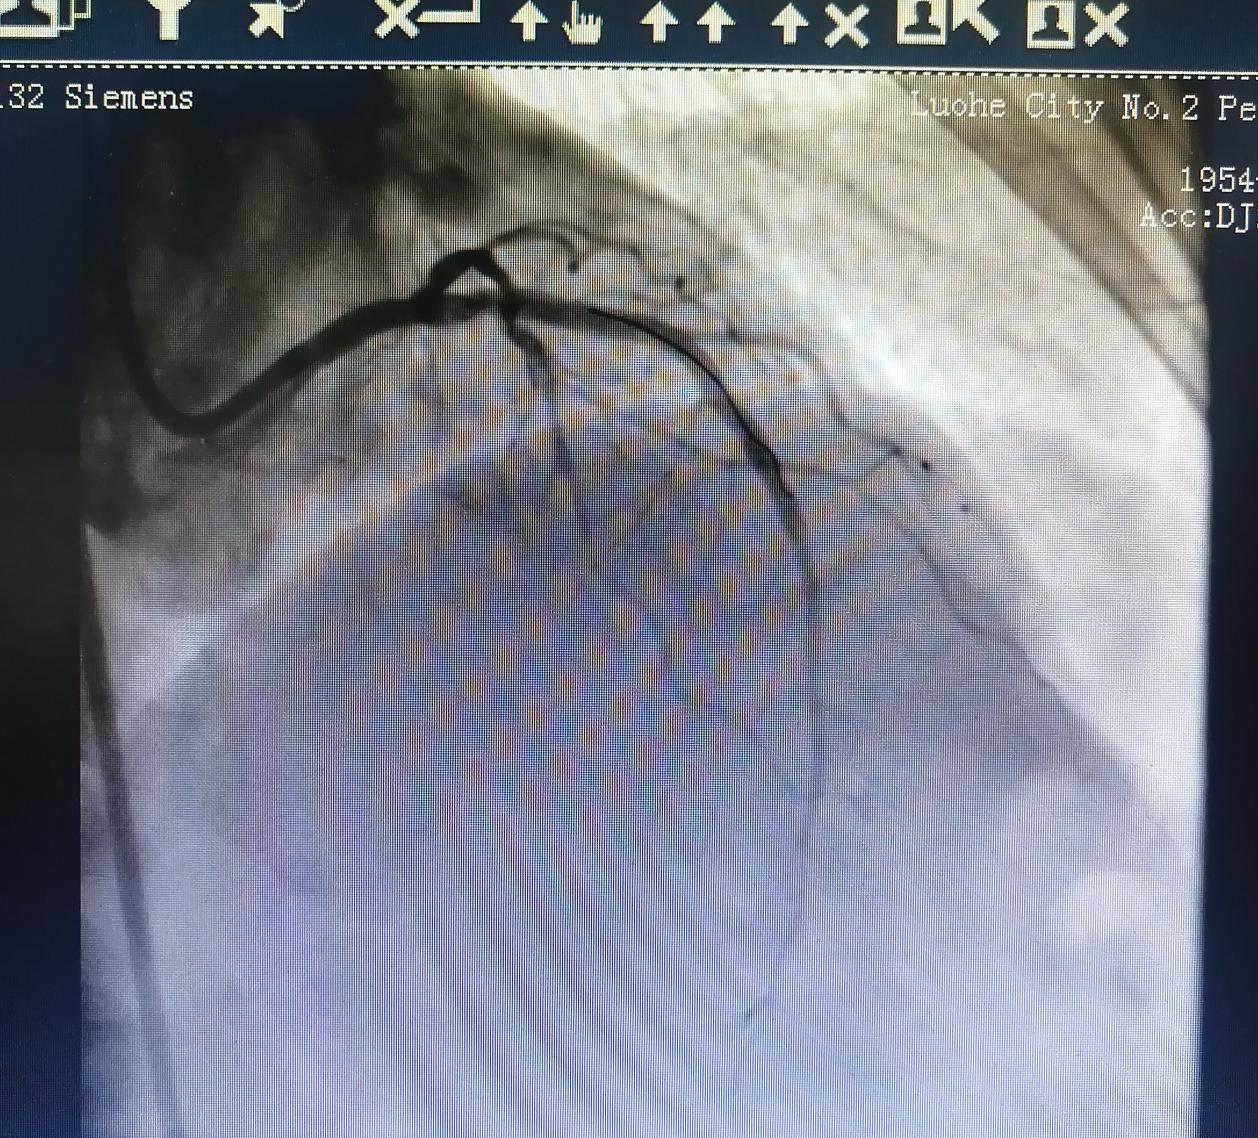

術(shù)前:

術(shù)后: